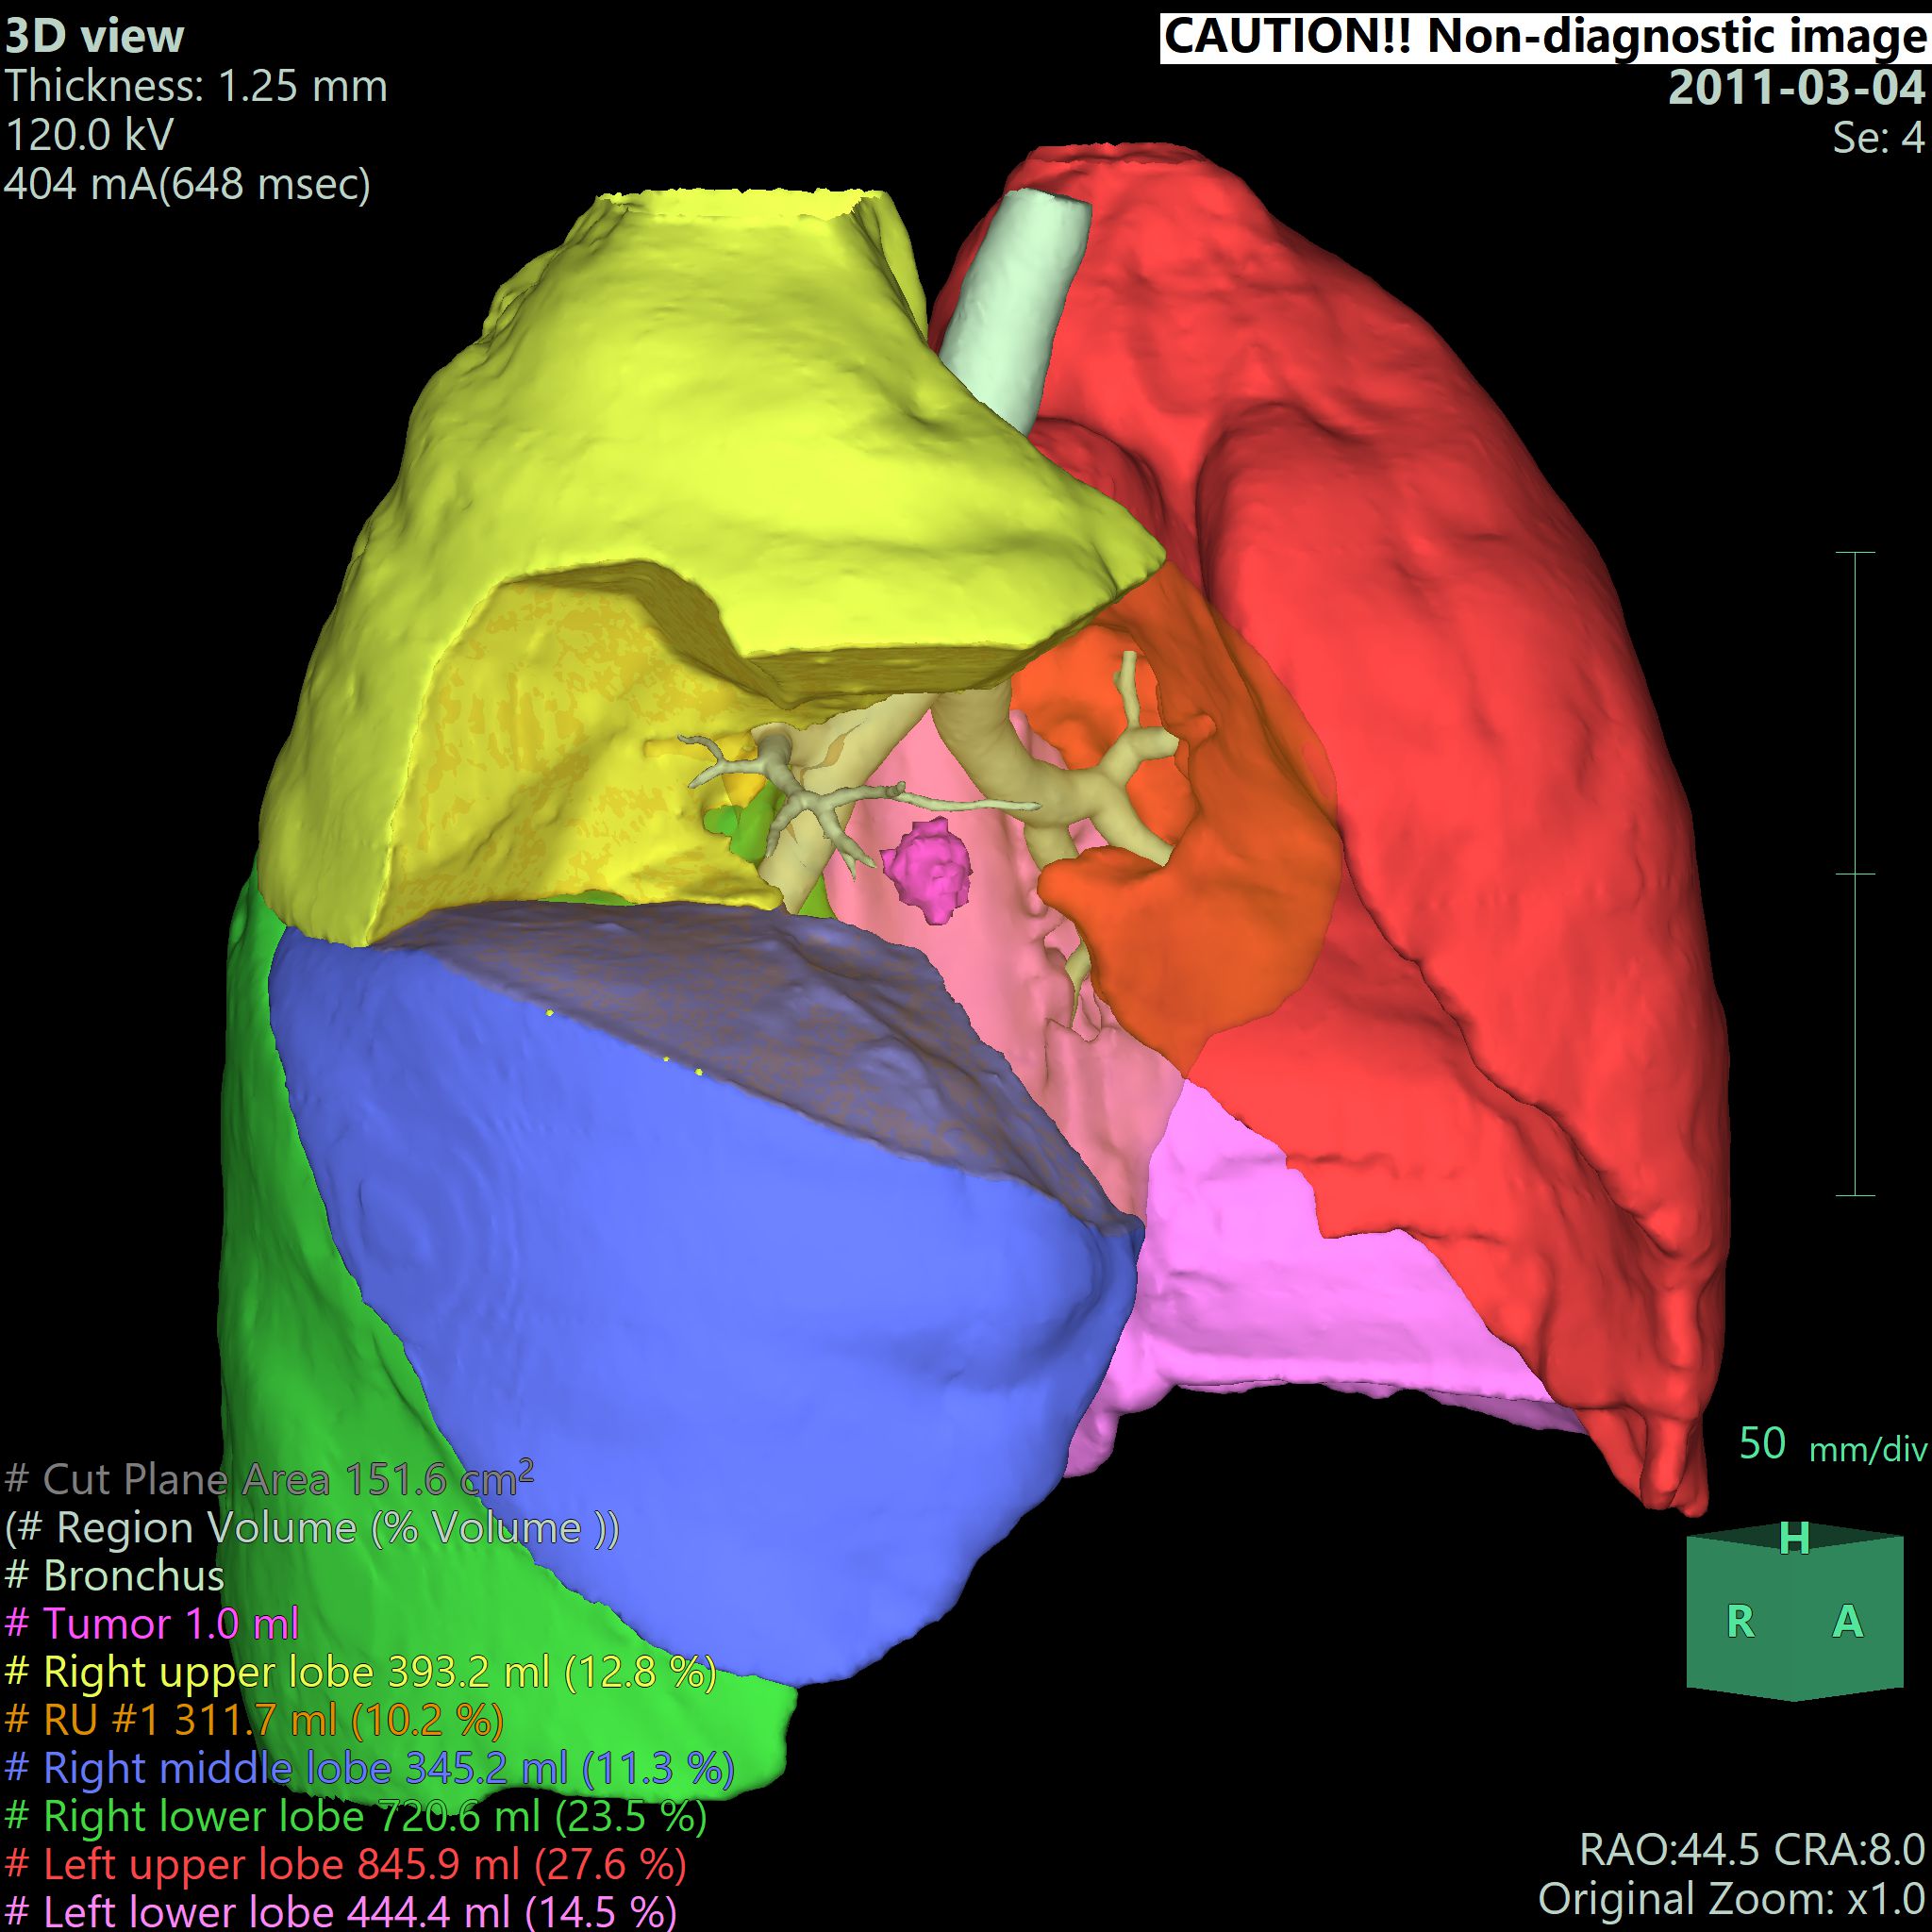

• - 자동으로 Lung의 좌우 및 5개의 Lobe를 분리하고 임의의 bronchus 지점을 기준으로 territory를 분리할 수 있습니다.

• - 조영 증강된 CT image를 사용하여 Lung, Airway, Vessel, tumor 등을 추출하고 3D로 재구성하고 결과를 관찰할 수 있습니다.

• - 임의의 Vascular point에서 territory를 분리하고 절제면, 절제면에서의 Vessel 및 territory의 volume 등을 측정할 수 있습니다.

• - 영역을 분리하고 tumor에서 plane 까지의 최소거리를 자동으로 측정할 수 있습니다.